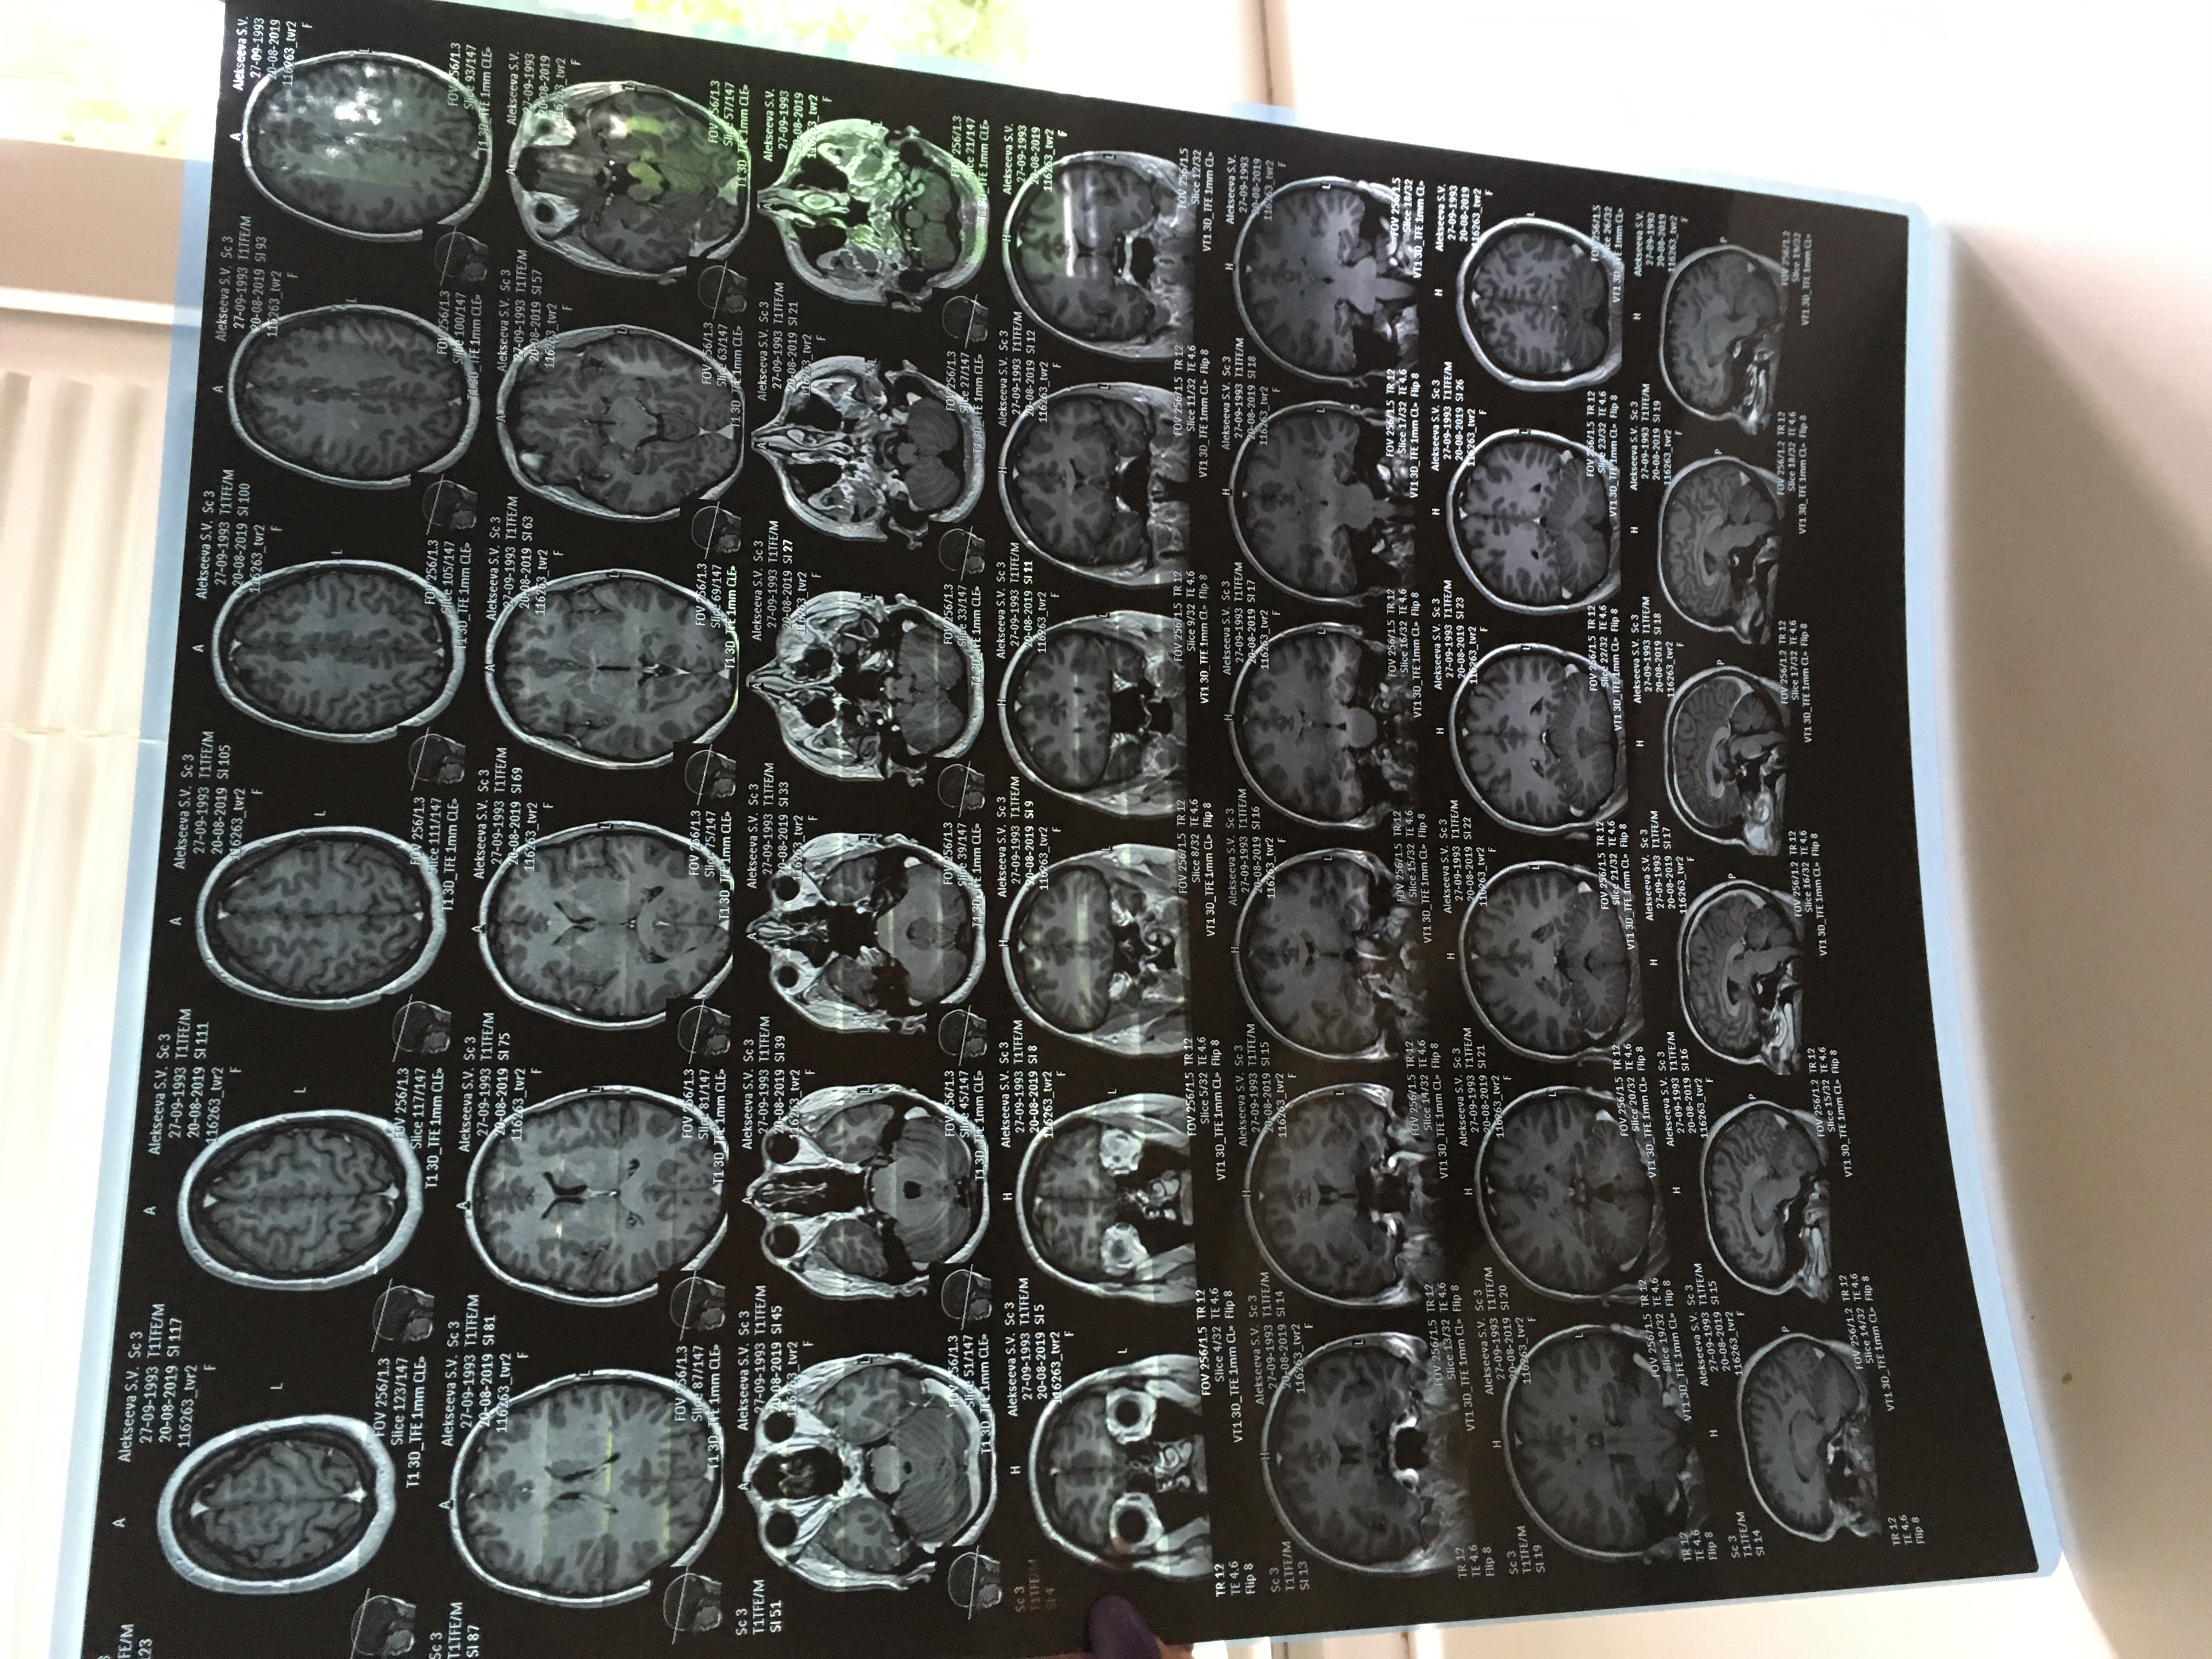

Помогите прочитать мрт ставят рассеянный склероз

Правильно ли?!

3D06933C-45D7-4546-9392-A9D02C679029.jpeg

133411B0-D039-4957-9999-307E9B4FD306.jpeg

1BB1DE8A-E797-484E-8A4A-0F9D1F99A269.jpeg

По тем снимкам, которым Вы сфотографировали, ничего сказать нельзя (нечитаемые).

Если необходимо, можно принести Ваши пленки или диск на консультацию (второе мнение).